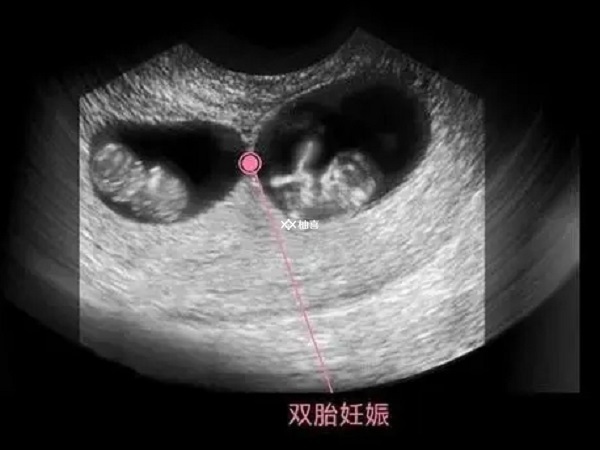

做试管婴儿通常将1到3个胚胎放入子宫腔以提高最终的成功率,如果其中两个胚胎都存活下来就是双胞胎。但是并不是所有人都可以移植2-3枚胚胎的,做试管婴儿如果想要移植两枚胚胎,对于女性朋友身体的要求并不低,具体如下:

不是所有做试管婴儿的女性都适合双胎移植,这主要和女性自身体质有关,女性身体素质好是基本要求,因为试管婴儿怀双胞胎风险高,容易发生妊娠期糖尿病和高血压,对胎儿生长发育会造成严重的情况,对母亲而言还可能会影响生命安全。